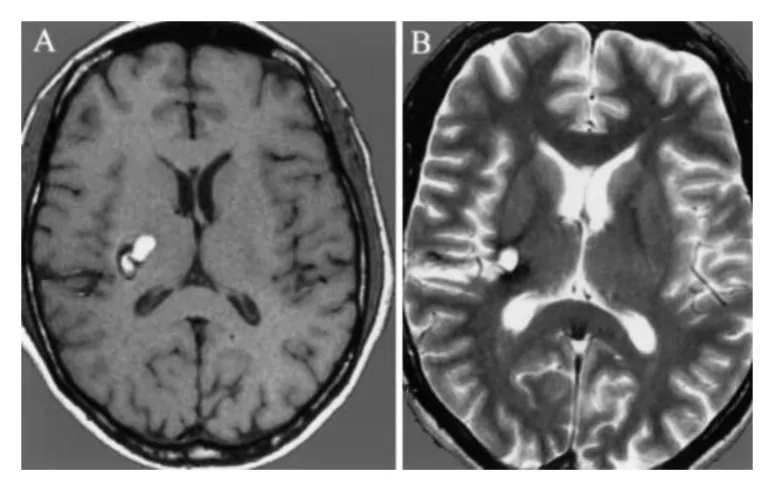

▼巴教授神经导航引导下切除基底神经节海绵状瘤。a,术前t1加权MR图像显示病变向内囊附近延伸。b,海绵状血管瘤瘤完全切除后的术后t2加权MRI